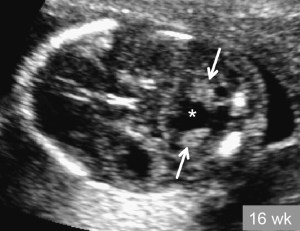

At the annual conference of the European Society of Human Reproduction and Embryology in Madrid, it was revealed that researchers from Israel and the Netherlands have kept ovarian tissue from aborted fetuses alive in the laboratory for several weeks.The chief researcher in the project, Dr. Tal Biron-Shental, said it was “theoretically possible” that with extra hormone treatment they could have produced mature eggs suitable for use in in vitro fertilization. Female fetuses develop ovaries after as little as 16 weeks in the womb, and harvesting eggs from them could be a boon for infertile couples.